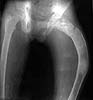

I am seeking help in managing a young patient 14 years old male with pathological subtrochanteric fracture neck femur. the problem is the severe varus deformity of the proximal femur the so called shepherd's crook deformity and also healing fracture shaft femur in midshaft region which he had sustained 6 months ago and was treated conservatively elsewhere. patient wants his deformity correction along with his fracture treatment if possible.

photo

The patient is delighted and working hard on knee flexion and has acheived up to 90 degrees now. Histopathology has come back as fibrous dysplasia. I am attaching the pre op and post op xrays.

preop